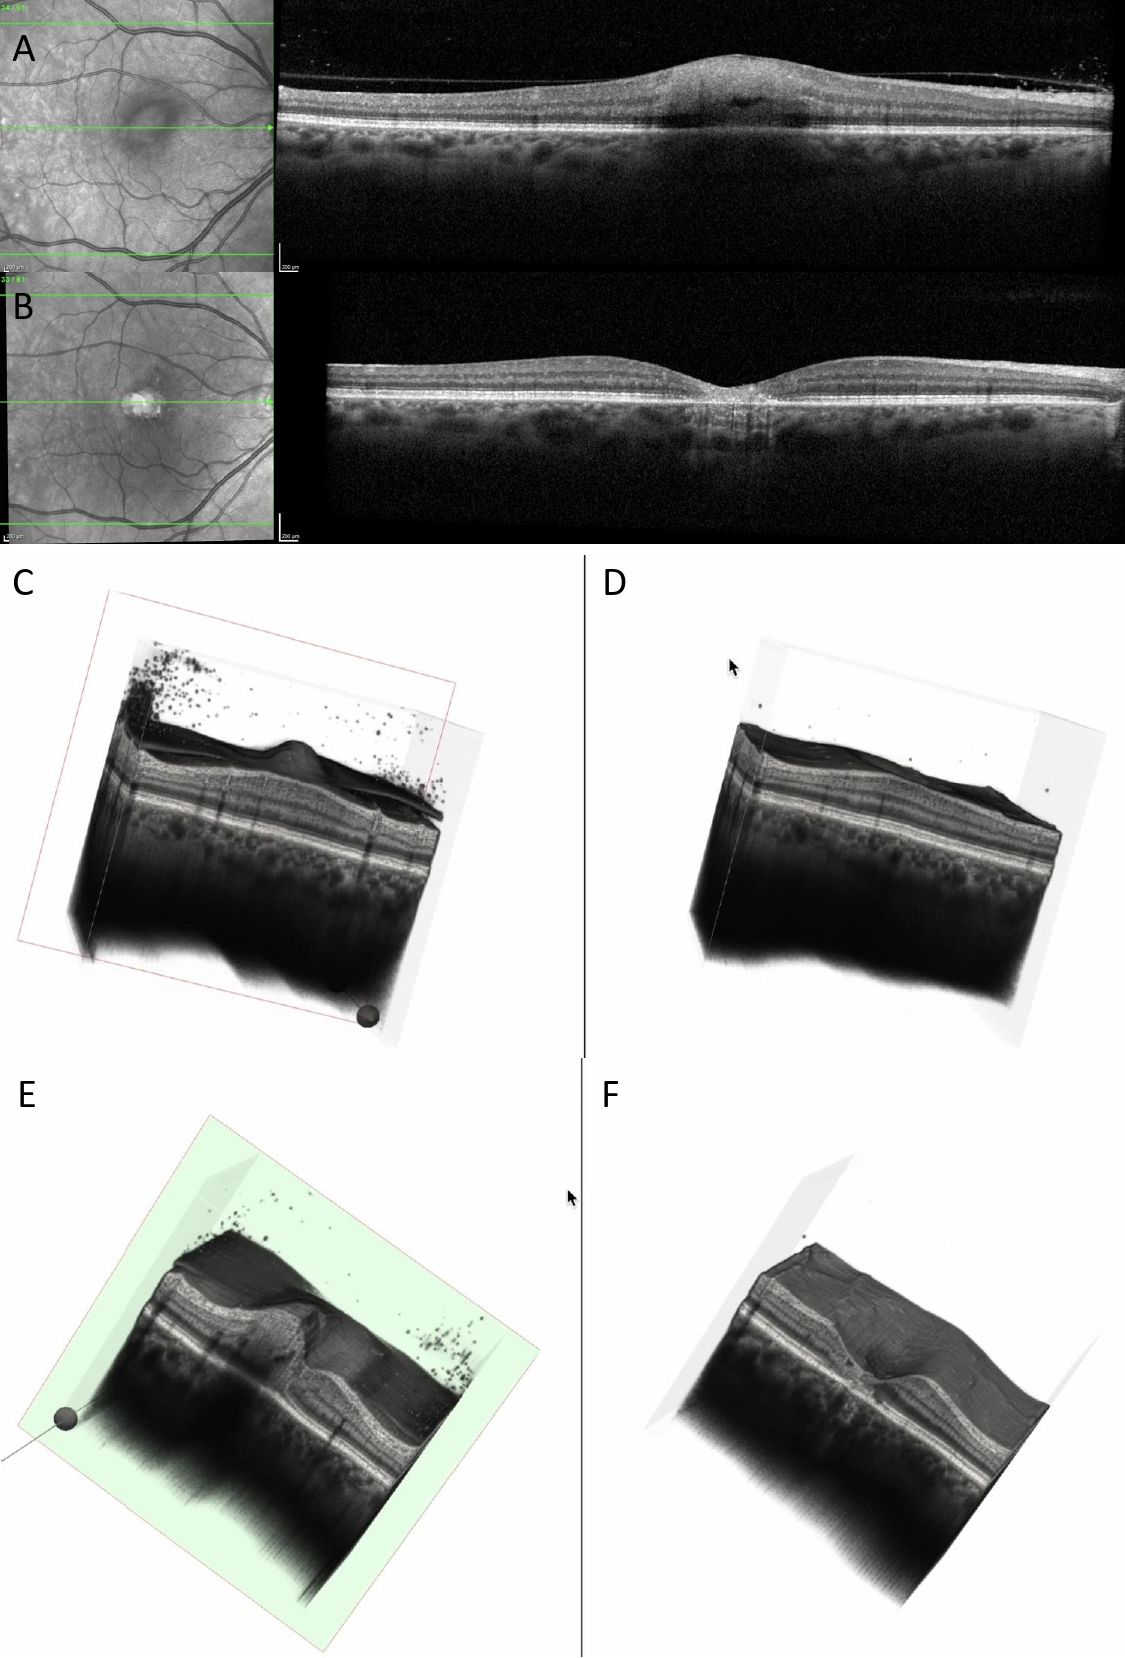

Figure 6. (A) OCT at baseline showing increased and hyperreflective retinal lesion, with a hyporeflective space. (B) OCT at 6 months showing decreased retinal thickness, hyperreflective gliotic tissue, discontinuity of RPE, EZ, ELM, and choroidal hypertransmission. (C) Three-dimensional reconstruction at baseline showing perifoveal increased retinal thickness, with vitreous cells and attached posterior hyaloid. (D) Three-dimensional reconstruction at 6 months showing enlarged foveal depression, disappearance of vitreous cells, and posterior vitreous detachment. (E) Cross-section of the 3D model at baseline showing increased perifoveal retinal thickness, choroidal shadowing, dispersed vitreous cells, and intraretinal hyporeflective spaces. (F) Cross-section of the 3D model at 6 months showing enlarged foveal depression with discontinuity of RPE, EZ, and ELM; the retinal vessels are prominent on the surface of the retina (see Supplementary Video S2).